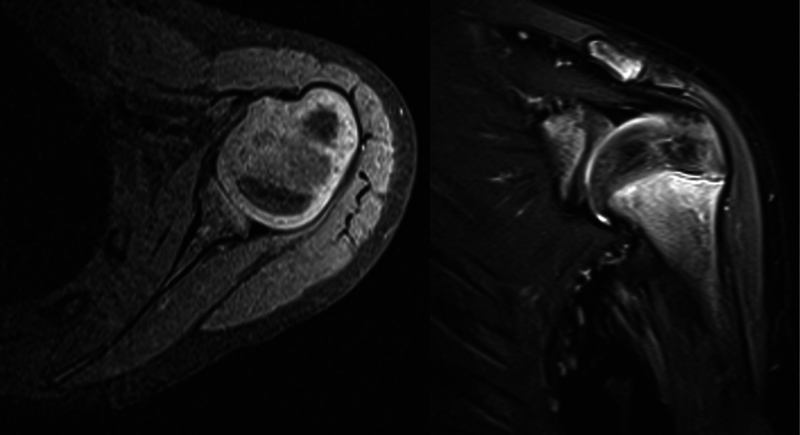

Abstract Image